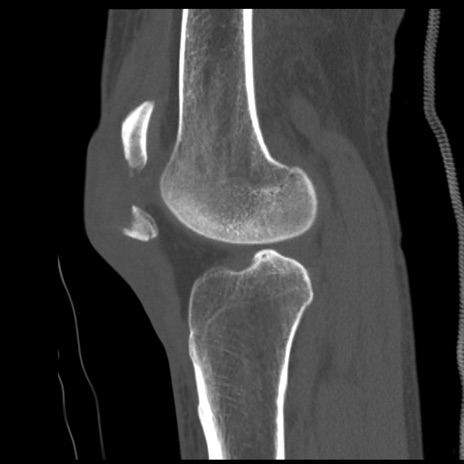

症例28 右膝関節CT(矢状断像)

右膝関節CT